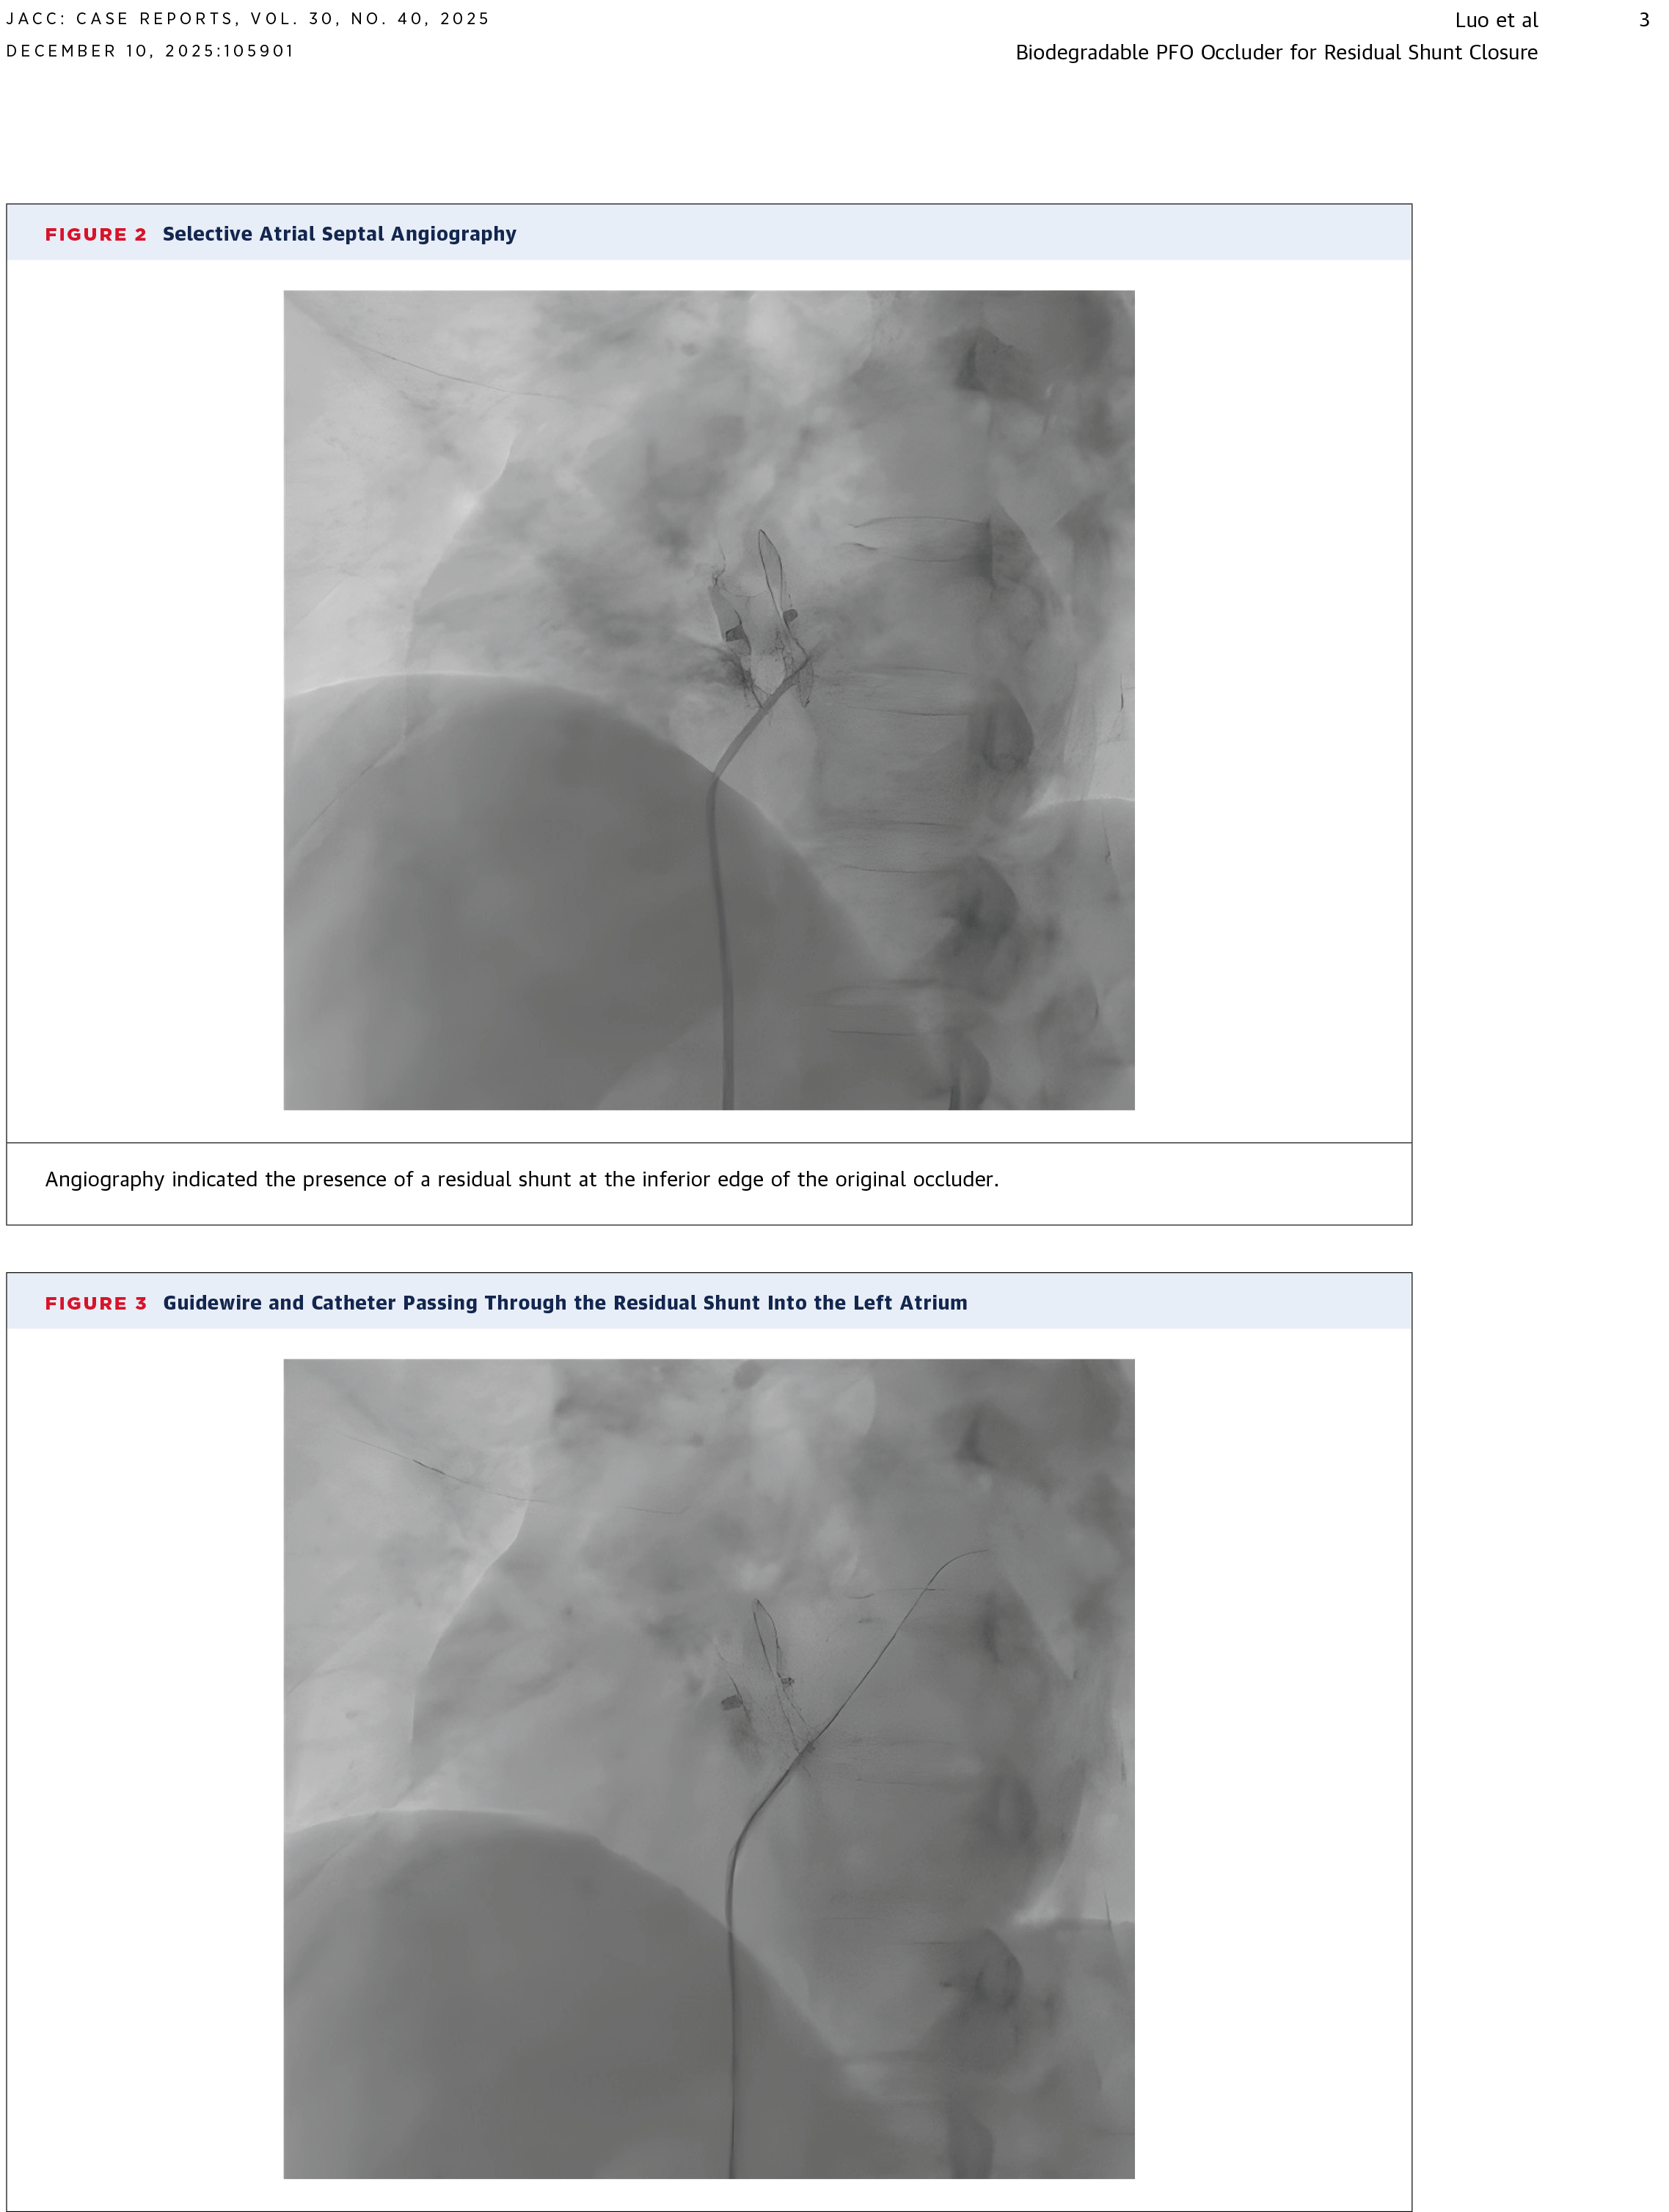

Percutaneous Closure of Residual Shunt After Patent Foramen Ovale Closure With a Biodegradable Occluder